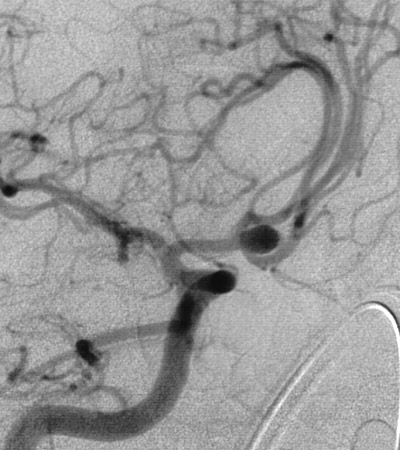

Here is a berry aneurysm located at the anterior communicating artery of the circle of Willis at the base of the brain.